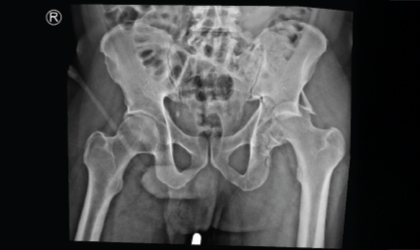

This 62 year old man had a fracture dislocation of his hip following a road traffic accident. He was referred to us two weeks later with a dislocated and fractured hip He underwent fixation of the fracure. The head was damaged and not viable after been dislocated for long. Hence he had a hip replacement as well These is a very complex surgery but he is back on his feet

On arrival, imaging revealed a severely dislocated hip with associated fracture. Due to the delay in treatment, the femoral head was non-viable and showed signs of damage.

We performed fixation of the fracture and, due to the compromised head of the femur, proceeded with a hip replacement during the same surgery. This complex procedure required precise alignment and implant positioning.